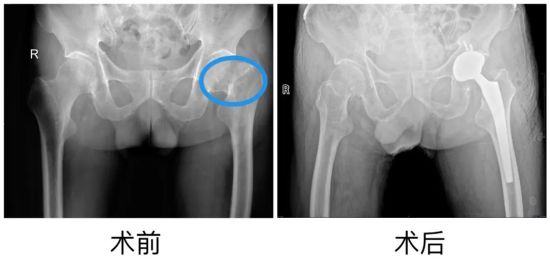

近日,山東大學(xué)第二醫(yī)院關(guān)節(jié)外科/運(yùn)動醫(yī)學(xué)科收治了一名72歲的股骨頸骨折患者,第一時間為患者開通綠色通道進(jìn)行多學(xué)科聯(lián)合診療(MDT),24小時內(nèi)即行髖關(guān)節(jié)置換手術(shù),患者術(shù)后24小時內(nèi)即可下地行走,恢復(fù)滿意。